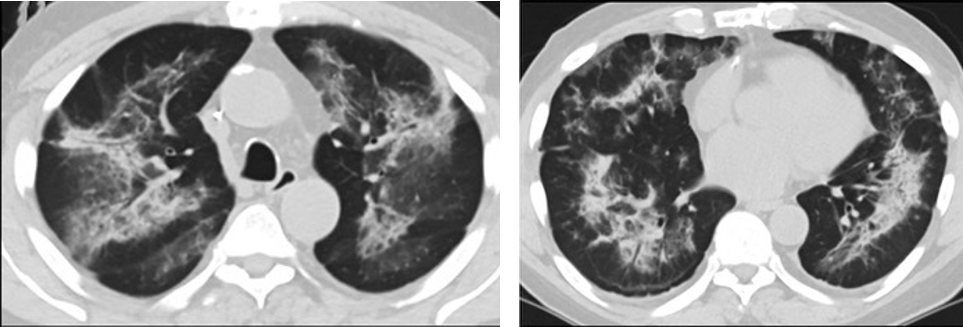

研究再次表明 电子烟肺炎与新冠肺炎相似 近日,一项研究通过梳理美国电子烟肺炎的患者症状和时间节点,发现三大疑点。再次表明,美国电子烟肺炎中存在新冠肺炎的可能性,不能排除。 疑点一,电子烟患者的CT影像和临床表现并不具有特异性。所谓美国电子烟肺炎患者,其实是对没有其他合理诊断证据、吸食电子烟肺炎患者的统称。这些患者在病发前90天内吸食了电子烟,尤其值得注意的是,部分患者的CT影像特征和临床表现与病毒性肺炎患者极其相似。 疑点二,中国科研工作者从60篇研究论文中筛选出142位电子烟肺炎患者的250张影像图片,邀请3位放射科权威专家,对上述全部影像图片、相关病人临床信息以及文献原文进行了仔细全面研究与审查,发现:16位被文献报道为电子烟肺炎的患者被专家判定为“病毒性感染”,即有可能是新冠肺炎的“疑诊患者”,其中更有5位临床症状和治疗情况相对完整的患者被判定为“中度可疑”。 因此在2019年美国报道的电子烟肺炎中存在病毒性感染的病例,而且不排除美国电子烟肺炎中存在新冠肺炎的可能性。 6天后的轴向CT平扫图像显示毛玻璃影变为实变和轻度结构扭曲。(同一病人CT影像) 疑点三,这16位患者均来自美国,其中4位患者的患病时间不详,其余12位的发病时间均在2020年以前。 针对美国早期新冠病例可能早于已知时间的报道和报告,美方始终没有回应。面对外界对美国电子烟肺炎和新冠肺炎的关系多有质疑,美国也一直对此避而不谈。 与电子烟肺炎纠扯不清 德堡“不能公布的细节” 美国电子烟肺炎谜团与德特里克堡存在怎样千丝万缕的联系?通过梳理电子烟肺炎出现的时间节点,二者联系不难发现。同一病人CT影像显示,中、下肺轴位CT平扫显示毛玻璃样混浊伴胸膜下保留(箭头)